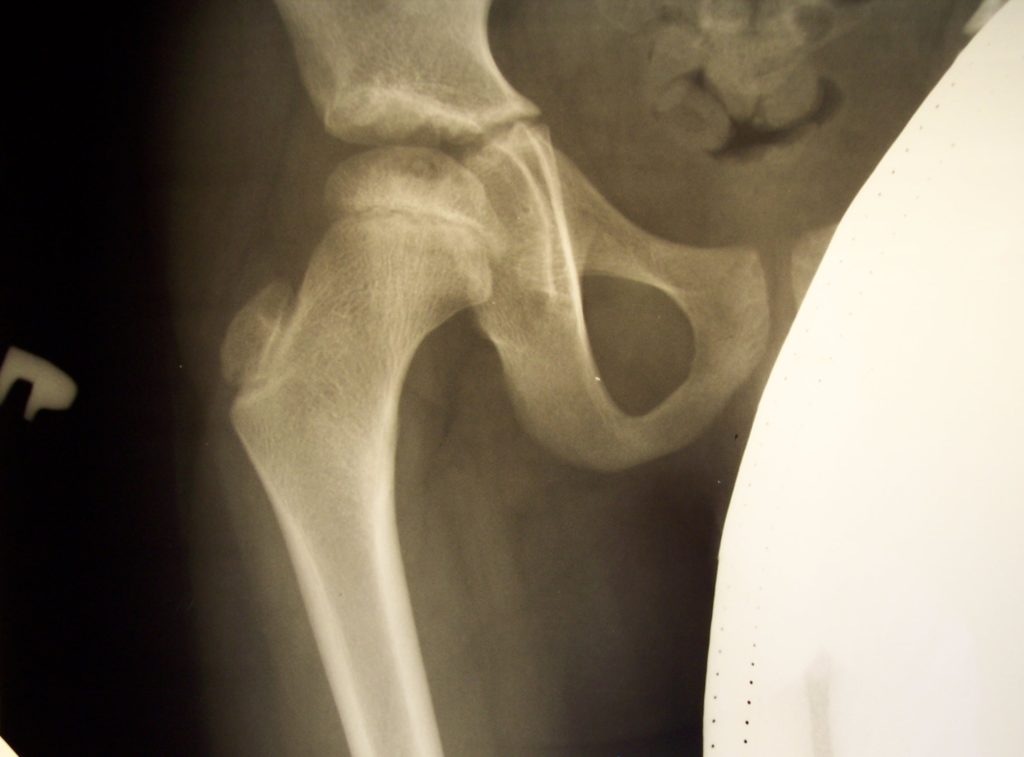

Рентгенограмма и КТ – исследование пациента К. 4 года, диагноз: болезнь Майера справа до начала лечения (25% остеонекроза пораженной головки).